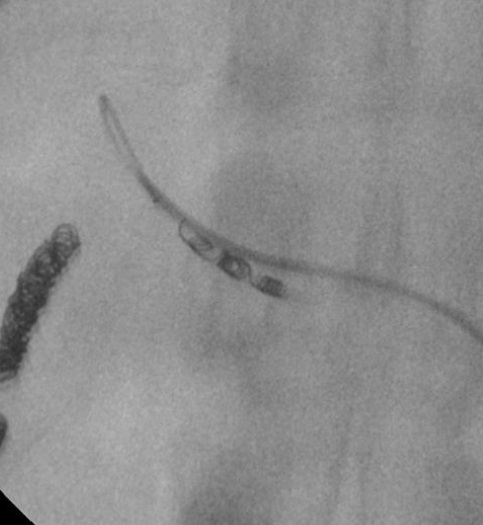

为增加微导管的可视性,许多导管头端加载金属标记带

金属标识到导管尖的距离也是微导管的一种追求

Prowler®微导管标识到导管尖的距离最短,这一特性提供透视下导管尖最精确的位置 微导管的尾部设计